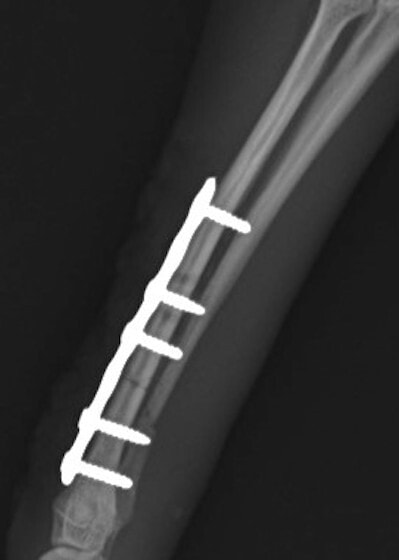

トイプードル 右遠位橈尺骨短斜骨折のALPSによる内固定

当院ではAdvanced Locking plate system(ALPS)と、Locking compression plate system(LCPS)という骨接合法で骨折症例の治療を行っています。

Advanced Locking Plate System

従来型のプレートのように広い面積で骨と接するプレートを用いて固定を行った場合、プレート下の骨はプレートとの接触面において血行が絶たれ壊死し、それがリモデリングされると骨密度が低下する。この骨密度の低下防ぐために、骨折部局所への血行を温存することの重要性が近年改めて認識されるようになってきている。Advaed Locking Plate System (ALPS)は従来型のプレートシステムの欠点を改良し、より使いやすく、より骨への血行を阻害しないようにというコンセプトで作られた。